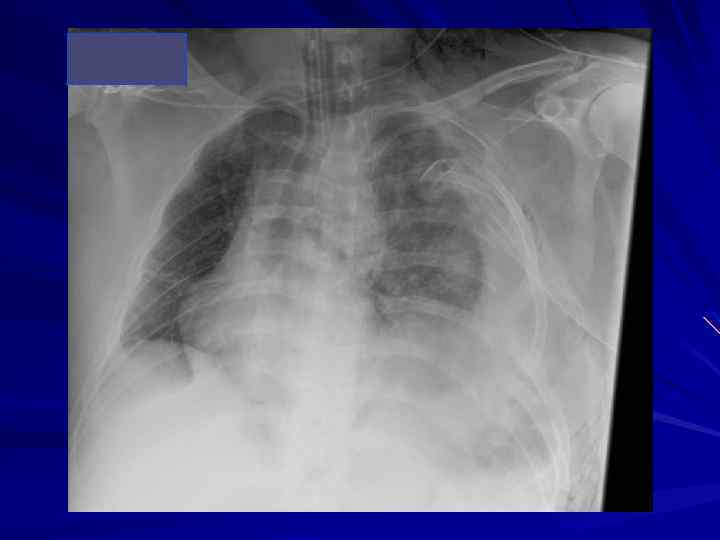

Пациент А. • Мужчина 53 года • ДТП • Жизненные параметры на месте происшествия (по записи бригады СМП): АД 114/80, ЧСС 130, ЧД 20, ШКГ 15

Приемный покой АД 74/48 | ЧСС 149 | ЧД 31 | Sp. O 2 88% | Темп. 37. 2°C Ø ШКГ 13 Ø Обширная рваная рана на затылке с продолжающимся кровотечением Ø Ушиб грудной клетки Ø Распространенная болезненность живота Ø Слабая пульсация на нижних конечностях Ø Обширная рваная рана на задней поверхности левого колена Ø Кровоподтеки и ссадины на обеих нижних конечностях

Операционная Ø Постоянная форма мерцательной артимии (варфарин? ) Ø Неэффективное самостоятельное дхание Интубация Ø Начат протокол массивной ИТТ Ø Катетеризация левой подключичной вены и лучевой артерии на правой руке Ø Рентген грудной клетки Ø Рентген таза

Ранние диагностика и лечение ОПЛ, обусловленного массивным переливанием препаратов крови Диагностика: Объем и состав трансфузионной терапии (>40% ОЦК) Нарушения оксигенации (Pa. O 2/Fi. O 2< 200 -300) Снижение «комплайнса» до 20 -30 мл/см вод. ст. и ниже Интенсивная терапия: При необходимости ВИВЛ в режиме по давлению с ПДКВ Метилпреднизолон болюс 2 -3 мг/кг с последующим круглосуточным титрованием в дозе 1 -2 мг/кг/сут с постепенной отменой «Консервативная» ИТТ - ограничение препаратов крови (только отмытые эритроциты), антилейкоцитарные фильтры Вирусинактивированная пулированная плазма (октаплас)